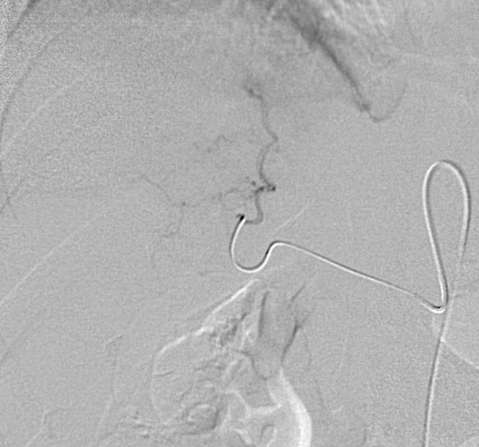

SIRT 在技术上的考虑首先要了解动脉解剖,采用微导管,使用使用高压注射器 另外要考虑Cone Beam CT的使用 6个月后,完全缓解 肝转移癌 增强CT Cone Beam CT

SIRT 在技术上的考虑首先要了解动脉解剖,采用微导管,使用使用高压注射器

另外要考虑Cone Beam CT的使用

Cone Beam CT